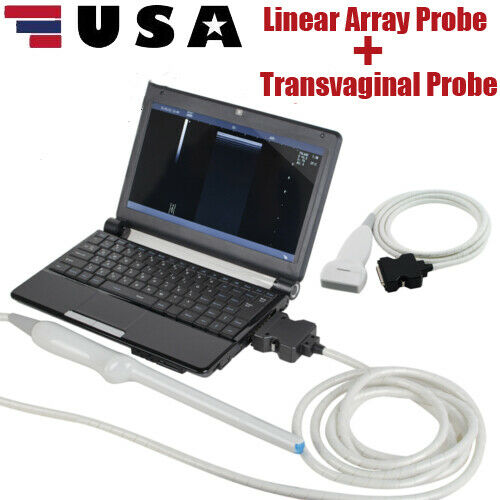

Pro Digital Laptop Ultrasound Machine Linear Array Probe + Transvaginal Probe

The Pro Digital Laptop Ultrasound Machine with a Linear Array Probe and Transvaginal Probe is a versatile and portable imaging system designed for a range of medical applications. This machine is suitable for both general diagnostics and specialized exams, including obstetrics and gynecology.

The included linear array probe provides high-resolution imaging, ideal for musculoskeletal, vascular, and soft tissue imaging. It delivers clear, detailed images for accurate diagnostics in various applications. The transvaginal probe is designed for internal imaging, offering clear visualization of the female reproductive organs, making it ideal for gynecological exams such as early pregnancy assessments and pelvic evaluations.

This laptop-style ultrasound machine is compact, lightweight, and portable, making it suitable for use in clinics, hospitals, or mobile medical units. It features an intuitive interface and customizable settings, streamlining the diagnostic process. This system combines advanced imaging capabilities with convenience and portability, making it an excellent choice for healthcare professionals.